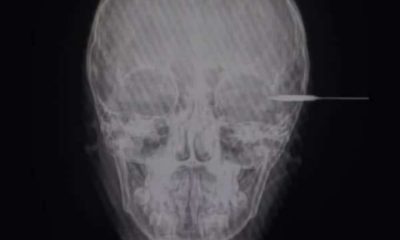

KANALKALIMANTAN.COM, AMUNTAI – Para orangtua mesti waspada alat bermain yang digunakan anak, Muhammad Luthfi Fadilah (8) tertancap anak panah kecil saat bermain dengan senapan rakitan yang...